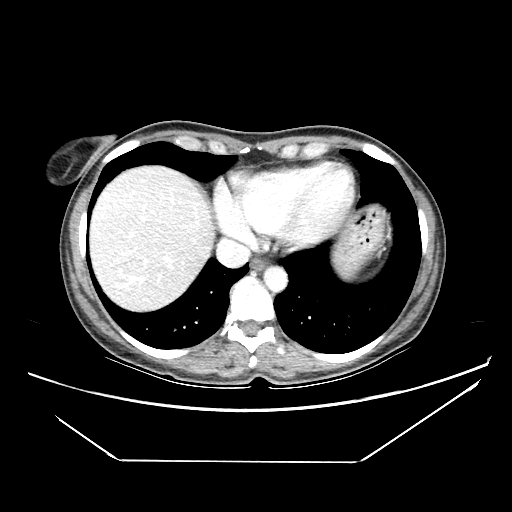

Image Grid

4Γ—3 grid: Rows show different image types (Original NATIVE, Reconstructed NATIVE, Original VENOUS, Generated VENOUS), Columns show windowing techniques (No Window, Lung Window, Mediastinum Window)

Generated VENOUS CT scan (A→B translation)

Full window (WL 1023.5, WW 4095 β†’ Low βˆ’1024, High +3071)

Lung window (WL -600, WW 1500 β†’ Low βˆ’1350, High +150)

Mediastinum window (WL 40, WW 400 β†’ Low βˆ’160, High +240)